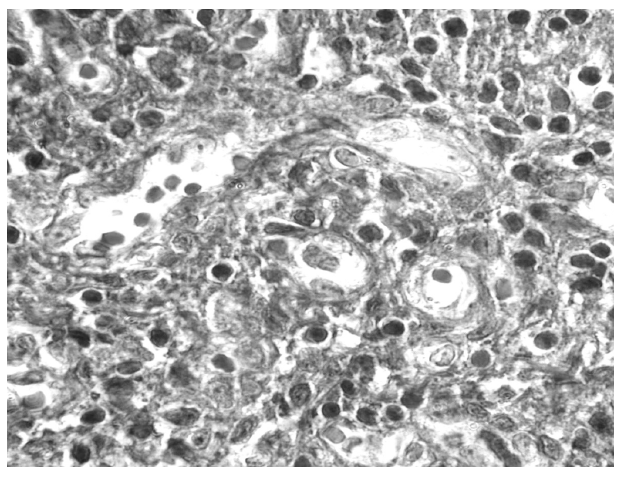

Паховые лимфатические узлы ВИЧ-инфицированных пациентов характеризовались повышенной плотностью. На разрезе отмечалось изменение гистоархитектоники лимфоузлов, их зоны определялись нечетко: паракортикальная зона не выявлялась, а мозговое вещество было значительно уменьшено в размерах. У всех больных наблюдался выраженный склероз в области ворот ПЛУ, а также утолщение капсулы и трабекул. Краевой и корковые синусы на большем протяжении были склерозированы. Склеротические процессы наблюдались в ПЛУ повсюду, начиная от перицеллюлярного коллагеногенеза до образования крупных участков фиброза во всех зонах, особенно в области ворот и трабекул. Наличие перицеллюлярной тонкопетлистой сети коллагеновых волокон свидетельствует о продолжающемся процессе фиброзирования лимфоузлов, несмотря на двухлетнюю эффективную АРТ (рис. 1).

Рис. 1. Сеть коллагеновых волокон в корковом веществе. Окраска по Массону. Ув. 10×100